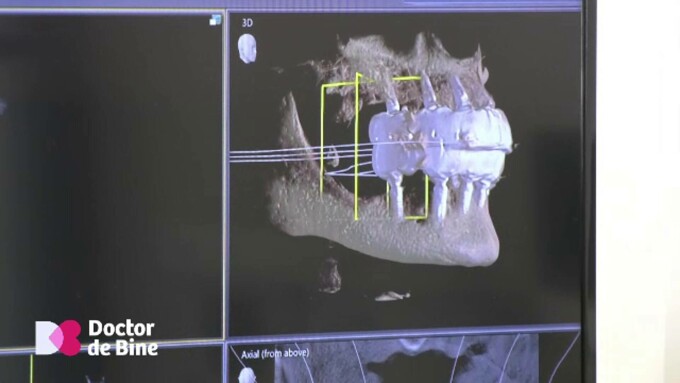

Cum se mișcă maxilarele când vorbim ori când mestecăm? Mișcările, înregistrate obiectiv, vor determina viitoarele lucrări dentare.

Așa-numitul arc facial digital potrivește fin toate structurile anatomice chiar și când un singur dinte a suferit.

Dr. Anca Rusu, medic chirurgie dento-alveolară: Arcul facial digital reprezintă o metodă de a capta digital relația mișcărilor dintre mandibulă și maxilar, dinamica. În masticație în vederea realizării unui diagnostic, dar și al unui plan de tratament, adică a unei lucrări protetice cât mai corecte.

Pentru a realiza o singură coroană dentară, dar și pentru reabilitări mari, complexe: maxilar–mandibulă. Imaginile obținute, 4D, arată relația în mișcare dintre structurile anatomice care participă la masticație ori la vorbire.

Dr. Anca Rusu,medic chirurgie dento-alveolară: Această achiziție de date e transmisă ulterior laboratorului dentar, datele fiind folosite pentru a realiza o lucrare dentară în corelație cu anatomia pacientului, deci foarte personalizată.

Ulterior, dinții reabilitați se armonizează cu fața. Dar și cu mișcările articulației temporo-mandibulare.

Dr. Monica Bratu, medic stomatolog protetică dentară: Aici, în fața urechilor, avem două balamale. Se numește articulația temporo-mandibulară, care trebuie respectată când facem niște reabilitări. Totul trebuie să fie în armonie cu restul anatomiei, adică cu forma craniului, în care se mișcă această balama. Cu caracteristicile mișcărilor date de mușchi, adică cât vrea să se întindă un mușchi, cât vrea să se întindă un ligament.

La finalul oricărui lucrări dentare, arcul facial digital e folosit pentru a verifica corectitudinea contactelor dintre dinți.